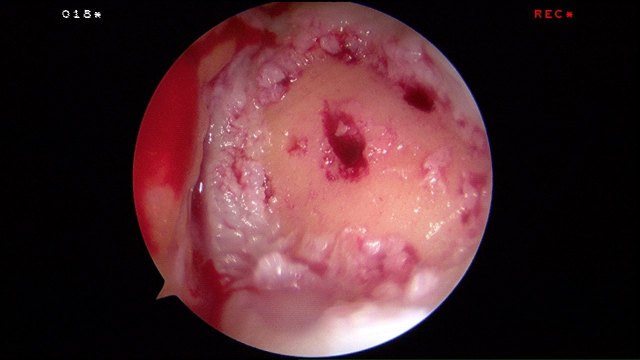

Arthroscopic enhanced microfracture was performed.

The hyalofast scaffold is cut to the right side, mixed with blood and inserted over the cartilage defect arthroscopically.